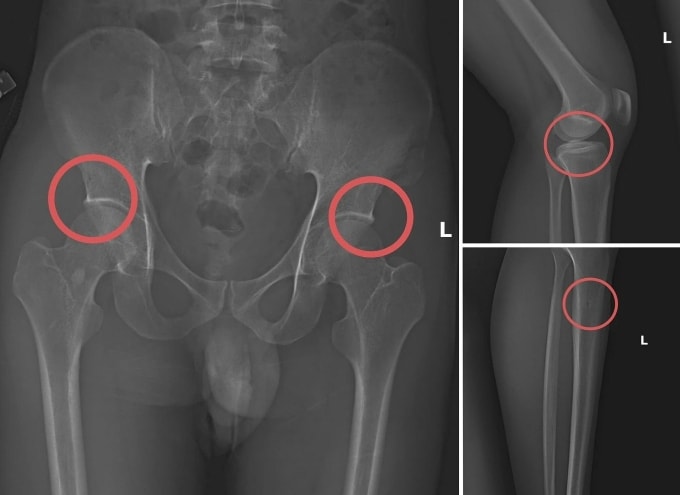

Tại đây, anh ta tiêm thuốc mê vào tĩnh mạch tay phải của người mua bảo hiểm để họ hôn mê. Sau đó, Châu dùng búa và kim tiêm đục, đâm vào vùng cơ thể đã thống nhất từ trước để tạo vết tổn thương trên xương cho nứt, vỡ. Thông thường, Châu sẽ làm rạn nứt, vỡ vùng xương chậu, đùi.

Khoảng 30 phút sau, các "chủ nhân bảo hiểm" sẽ tỉnh lại. Châu hướng dẫn họ tạo ra các vụ tai nạn "hết sức tự nhiên" như bị điện giật ngã làm gãy xương chậu, đi suối ngã gãy chân. Tiếp đến, họ gọi nhờ người đưa đến Trung tâm y tế, bệnh viện khám và điều trị để lấy bệnh án.